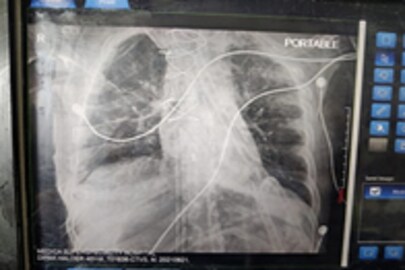

#কলকাতা: বাংলায় তৈরি হল এক নতুন ইতিহাস। পূর্ব ভারতে প্রথম কলকাতাতেই সফলভাবে ফুসফুসের প্রতিস্থাপন (Lung Transplant) করা হল। ২০ সেপ্টেম্বর কলকাতার মেডিকা সুপারস্পেশ্যালিটি হাসপাতালে (Medica Superspecialty Hospital) ৪৬ বছরের দীপক হালদারের (Dipak Halder) দু'টি ফুসফুসই সফলভাবে প্রতিস্থাপন করা হয়েছে। জানা গিয়েছে যে, গুজরাতের সুরাত থেকে এয়ার অ্যাম্বুলেন্সের (Air Ambulance) মাধ্যমে ফুসফুস দু'টিকে কলকাতার এই বেসরকারি হাসপাতালে নিয়ে আসা হয়।

দীপক হালদারের করোনার চিকিৎসা চলছিল এবং তিনি ইসিএমও (ECMO) সাপোর্টে ছিলেন। সফলভাবে তাঁর দু'টি ফুসফুস প্রতিস্থাপন করে কলকাতার এই সুপারস্পেশ্যালিটি হাসপাতাল এক অন্যন্য নজির সৃষ্টি করেছে। পূর্ব ভারতের মধ্যে কলকাতাতেই প্রথম সফলভাবে, এমন ফুসফুসের প্রতিস্থাপন করা সম্ভব হল। এই অপারেশনের জন্য বিখ্যাত কার্ডিয়াক সার্জারি স্পেশালিস্ট ডাক্তারদের (Cardiac Surgery Doctor) নিয়ে গড়া হয়েছিল কার্ডিয়াক ক্রিটিকাল কেয়ার টিম (Cardiac Critical Care Team)।